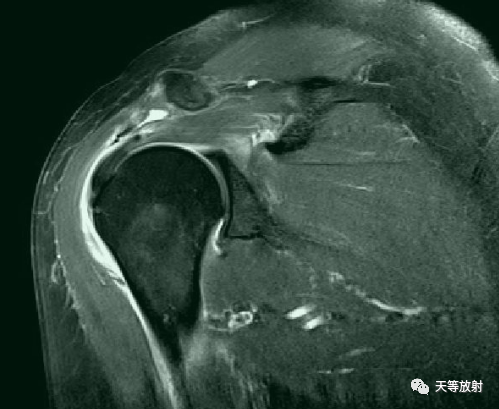

正常冈上肌MRI表现

肩峰撞击综合征的MR表现

冈上肌变性

肩袖信号增高

冈上肌关节面部分撕裂

滑囊面部分撕裂

冈上肌完全撕裂

冈上肌全层撕裂伴肩撞(骨赘形成)

冈上肌全层撕裂MRI间接关节造影表现